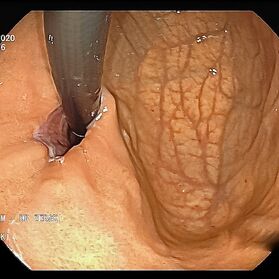

Die Gastroskopie (Magenspiegelung) hat sich als sicheres Standardverfahren zur Beurteilung des oberen Verdaungstraktes bei vielfältigen Krankheitsbildern und Fragestellungen fest etabliert.

Mit einer Gastroskopie werden Speiseröhre, Magen und Zwölfingerdarm (der oberste Teil des Dünndarms) untersucht. Dazu wird ein geschmeidig biegsames, schlankes Endoskop mit eingebauter Digitalkamera durch den Mund eingeführt. Minimalste Veränderungen können dabei gesehen werden, die im Röntgenbild oder einer Kernspintomographie (MRT) noch gar nicht erkannt werden. Im Vergleich zu anderen bildgebenden Untersuchungsverfahren ist bei der Endoskopie neben der wichtigen optischen Beurteilung auch die sofortige Möglichkeit gegeben, Gewebeproben aus auffälligen Bereichen zu entnehmen. Dazu wird eine kleine Spezialzange durch einen Kanal im Endoskop geschoben und die Probe ganz präzise aus dem entsprechenden Gewebe gewonnen. Da die Schleimhäute schmerzunempfindlich sind, spüren Sie davon nichts. Die Proben werden von Spezialisten mikroskopisch untersucht und ermöglichen dann eine zielgerichtete Therapie; zum Beispiel wenn eine Magenschleimhautentzündung durch eine chronische Infektion ausgelöst wird, die mit einer Antibiotikakur erfolgreich behandelt werden kann.